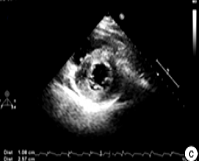

心脏超声

诊断室壁运动异常、左右心室大小及功能、心包积液、瓣膜返流

血流动力学恶化时需复查